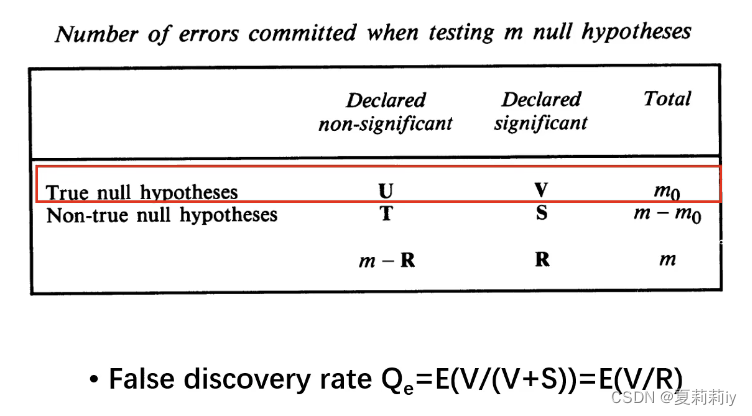

2.2. 多重比较矫正(Multiple Comparison Correction)

②False Discovery Rate(FDR):有很多种方法(太多且复杂就不一一例举,仅给出严老师PPT里给的方法),比Bonferroni更为温和实用。在DPABI_VIEW里Cluster可选FDR矫正